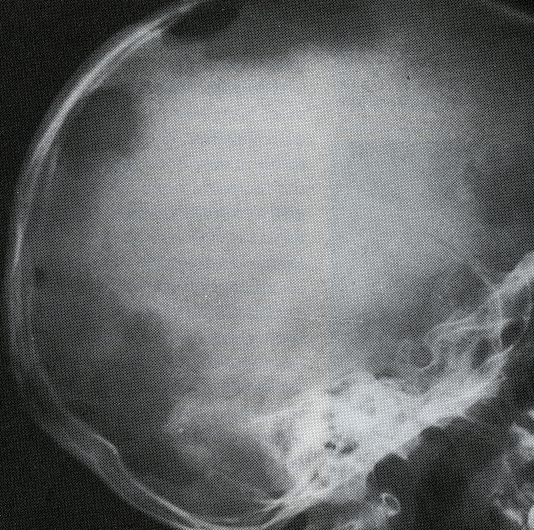

The actual cause of Hand-Schuller-Christian disease is unknown, and several blood abnormalities are present. The typical onset of symptoms occurs between the ages of three and six years old, and boys are affected by the condition marginally more often than females. Diabetes insipidus and skeletal abnormalities are frequently observed in patients with this condition. The patients mostly complain about the unnatural protrusion of the eyes. CT scans are especially useful for detecting and characterizing bone lesions as well as soft tissue involvement.

- Chest X-ray.

- Skeletal survey.